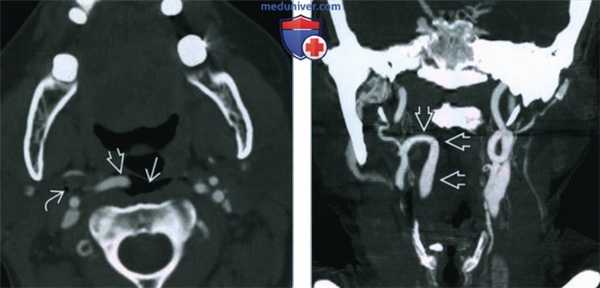

(Слева) КТ-ангиография, аксиальная проекция, пациентка 62 лет, получившая колющее ранение правой половины шеи, проникающее в глотку. В заглоточном и сонном пространствах имеется газ. В заглоточном пространстве случайно обнаружена медиализированная, извитая сонная артерия.

(Справа) КТ-ангиография, коронарная проекция. Правая внутренняя сонная артерия изгибается и вступает в заглоточное пространство. При изучении коронарных срезов сосудистая природа аномалии становится особенно явной. (Слева) КТ с КУ, аксиальная проекция. Левая внутренняя сонная артерия В смещена в медиальную сторону. Обратите внимание, что на уровне носоглотки она расположена очень близко к слизистой оболочке. О подобных аномалиях необходимо указать в заключении, так как это позволит избежать ятрогенного повреждения артерии при операции на глотке.

(Справа) КТ без КУ, аксиальная проекция. Классический пример «целующихся» извитых сонных артерий. В заглоточном пространстве артерии касаются друг друга на уровне средней линии.

(Справа) КТ-ангиография, коронарная проекция. Правая внутренняя сонная артерия изгибается и вступает в заглоточное пространство. При изучении коронарных срезов сосудистая природа аномалии становится особенно явной.

(Слева) КТ с КУ, аксиальная проекция. Левая внутренняя сонная артерия В смещена в медиальную сторону. Обратите внимание, что на уровне носоглотки она расположена очень близко к слизистой оболочке. О подобных аномалиях необходимо указать в заключении, так как это позволит избежать ятрогенного повреждения артерии при операции на глотке.